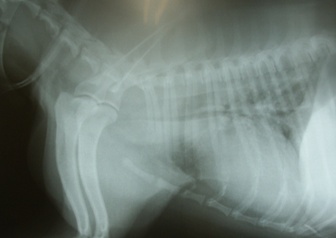

処置:Ultraflex Diamond留置(図11)

合併症:ステント破損(図12)したが、気管支拡張療法で気管開存(図13)。現在follow中(877日間)。

図11 症例2の第10病日。Ultraflex Diamondを胸部気管に留置。

図12 症例2の第18病日。ステントの破損。

図13 症例2の第45病日。気管支拡張療法の結果、気管が再び開存してきた。